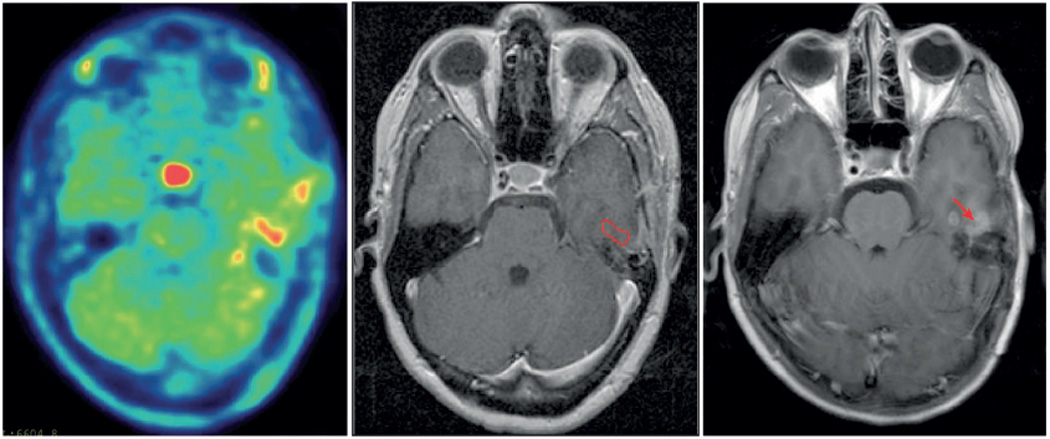

Non-invasive in vivo measurement of glutamine uptake can be achieved in human glioma patients using radiolabelled 4-18F-(2S,4R)-fluoroglutamine (18F-FGln) (Figures 2 and 3). 18F-FGln uptake is increased in gliomas compared to normal brain enabling clear tumor to background delineation88. Significant reduction in 18F-FGln uptake was seen following chemo-radiation, which correlated with reduced tumor cell burden. Tumor uptake in gliomas can depend on the integrity of the blood-brain barrier. Experiments in animal models and a small cohort of human subjects shows that uptake of 18F-FGln may not directly depend on disruption of the blood-brain barrier, but need further characterization in a larger patient cohorts88. Further, in human subjects, 18F-FGln uptake distinguished patients with progressive disease from stable patients with minimal to no 18F-FGln PET avidity (Figure 4), in contrast to 18F-FDG PET or conventional MRI, making this metabolic imaging modality a potentially valuable clinical tool in the management of patients with glioma

Figure 4. PET imaging with 18F-labeled Glutamine in a patient with a low-grade glioma with malignant transformation to high-grade glioma.

(A) T1 gadolinium-enhanced brain MRI of a patient with a history of a WHO grade II low-grade glioma diagnosed 2 years prior, now with malignant transformation identified by a new focus of enhancement (red arrow). (B) 18F-FGln PET shows uptake within the corresponding area of contrast-enhancement 90 minutes post tracer-injection. Subsequent surgical resection confirmed high-grade transformation.